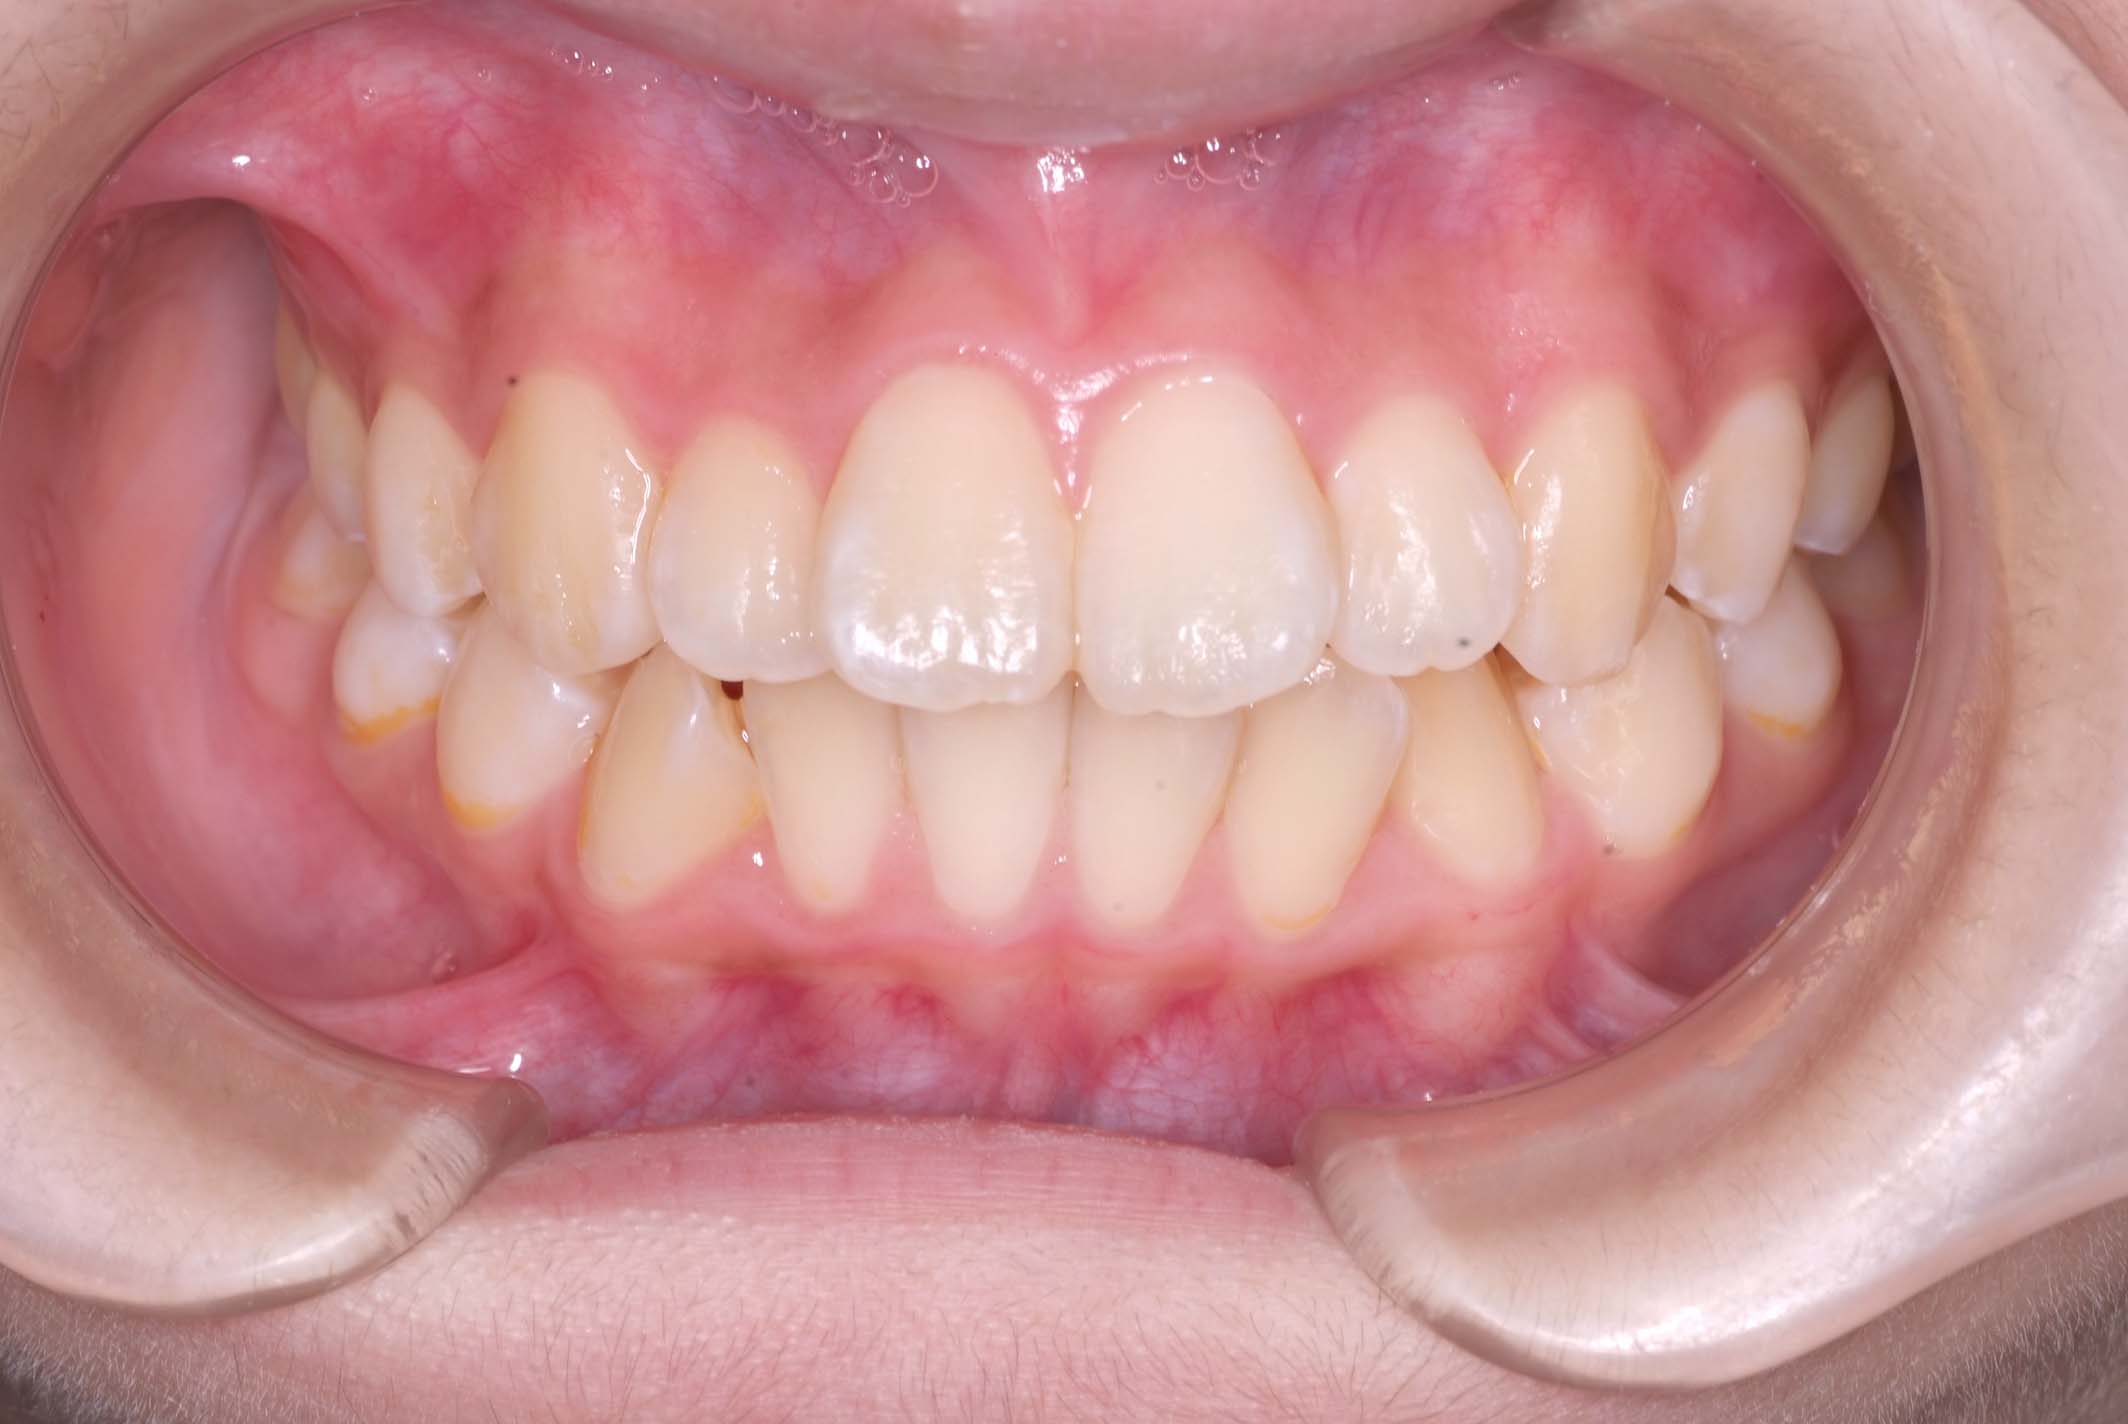

初診時年齢8才の女子で、前歯部開咬を気にして来院されました。

検査の結果、前歯部開咬と正中離開と上下顎前歯唇側傾斜を伴うアングルⅡ級1類不正咬合と診断しました。

前期治療は、リンガルアーチで正中離開を改善し、その後は歯列矯正用咬合誘導装置(マイオブレース)を使用して舌のトレーニングを行いました。後期治療は、上下左右4番を抜歯の上、セルフライゲーションブラケット装置(クリアティ・ウルトラ)で行いました。治療期間は前後期合わせて6年6ヶ月でした。通院回数:60回。